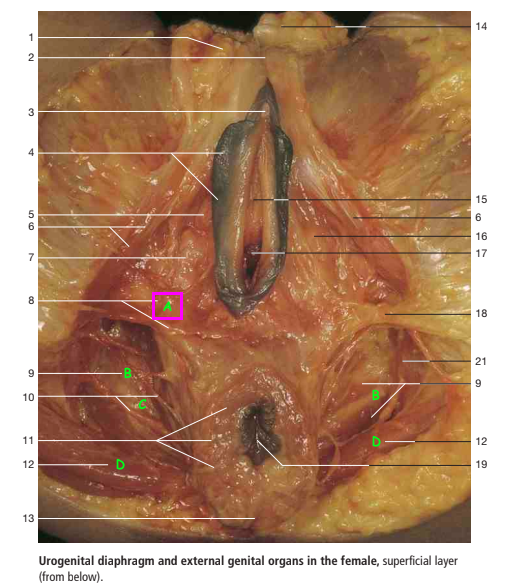

Label A-E of female anatomy [5]

A

A: bulb of the vestibule

B: levator ani

C: Obturator internus muscle

D: Left ureteric orifice

E: Muscular coat of urinary bladder

Label A-E

A: vagina

B: crus of clitoris

C: labia minoria

D: glands of clitoris

E: cervix